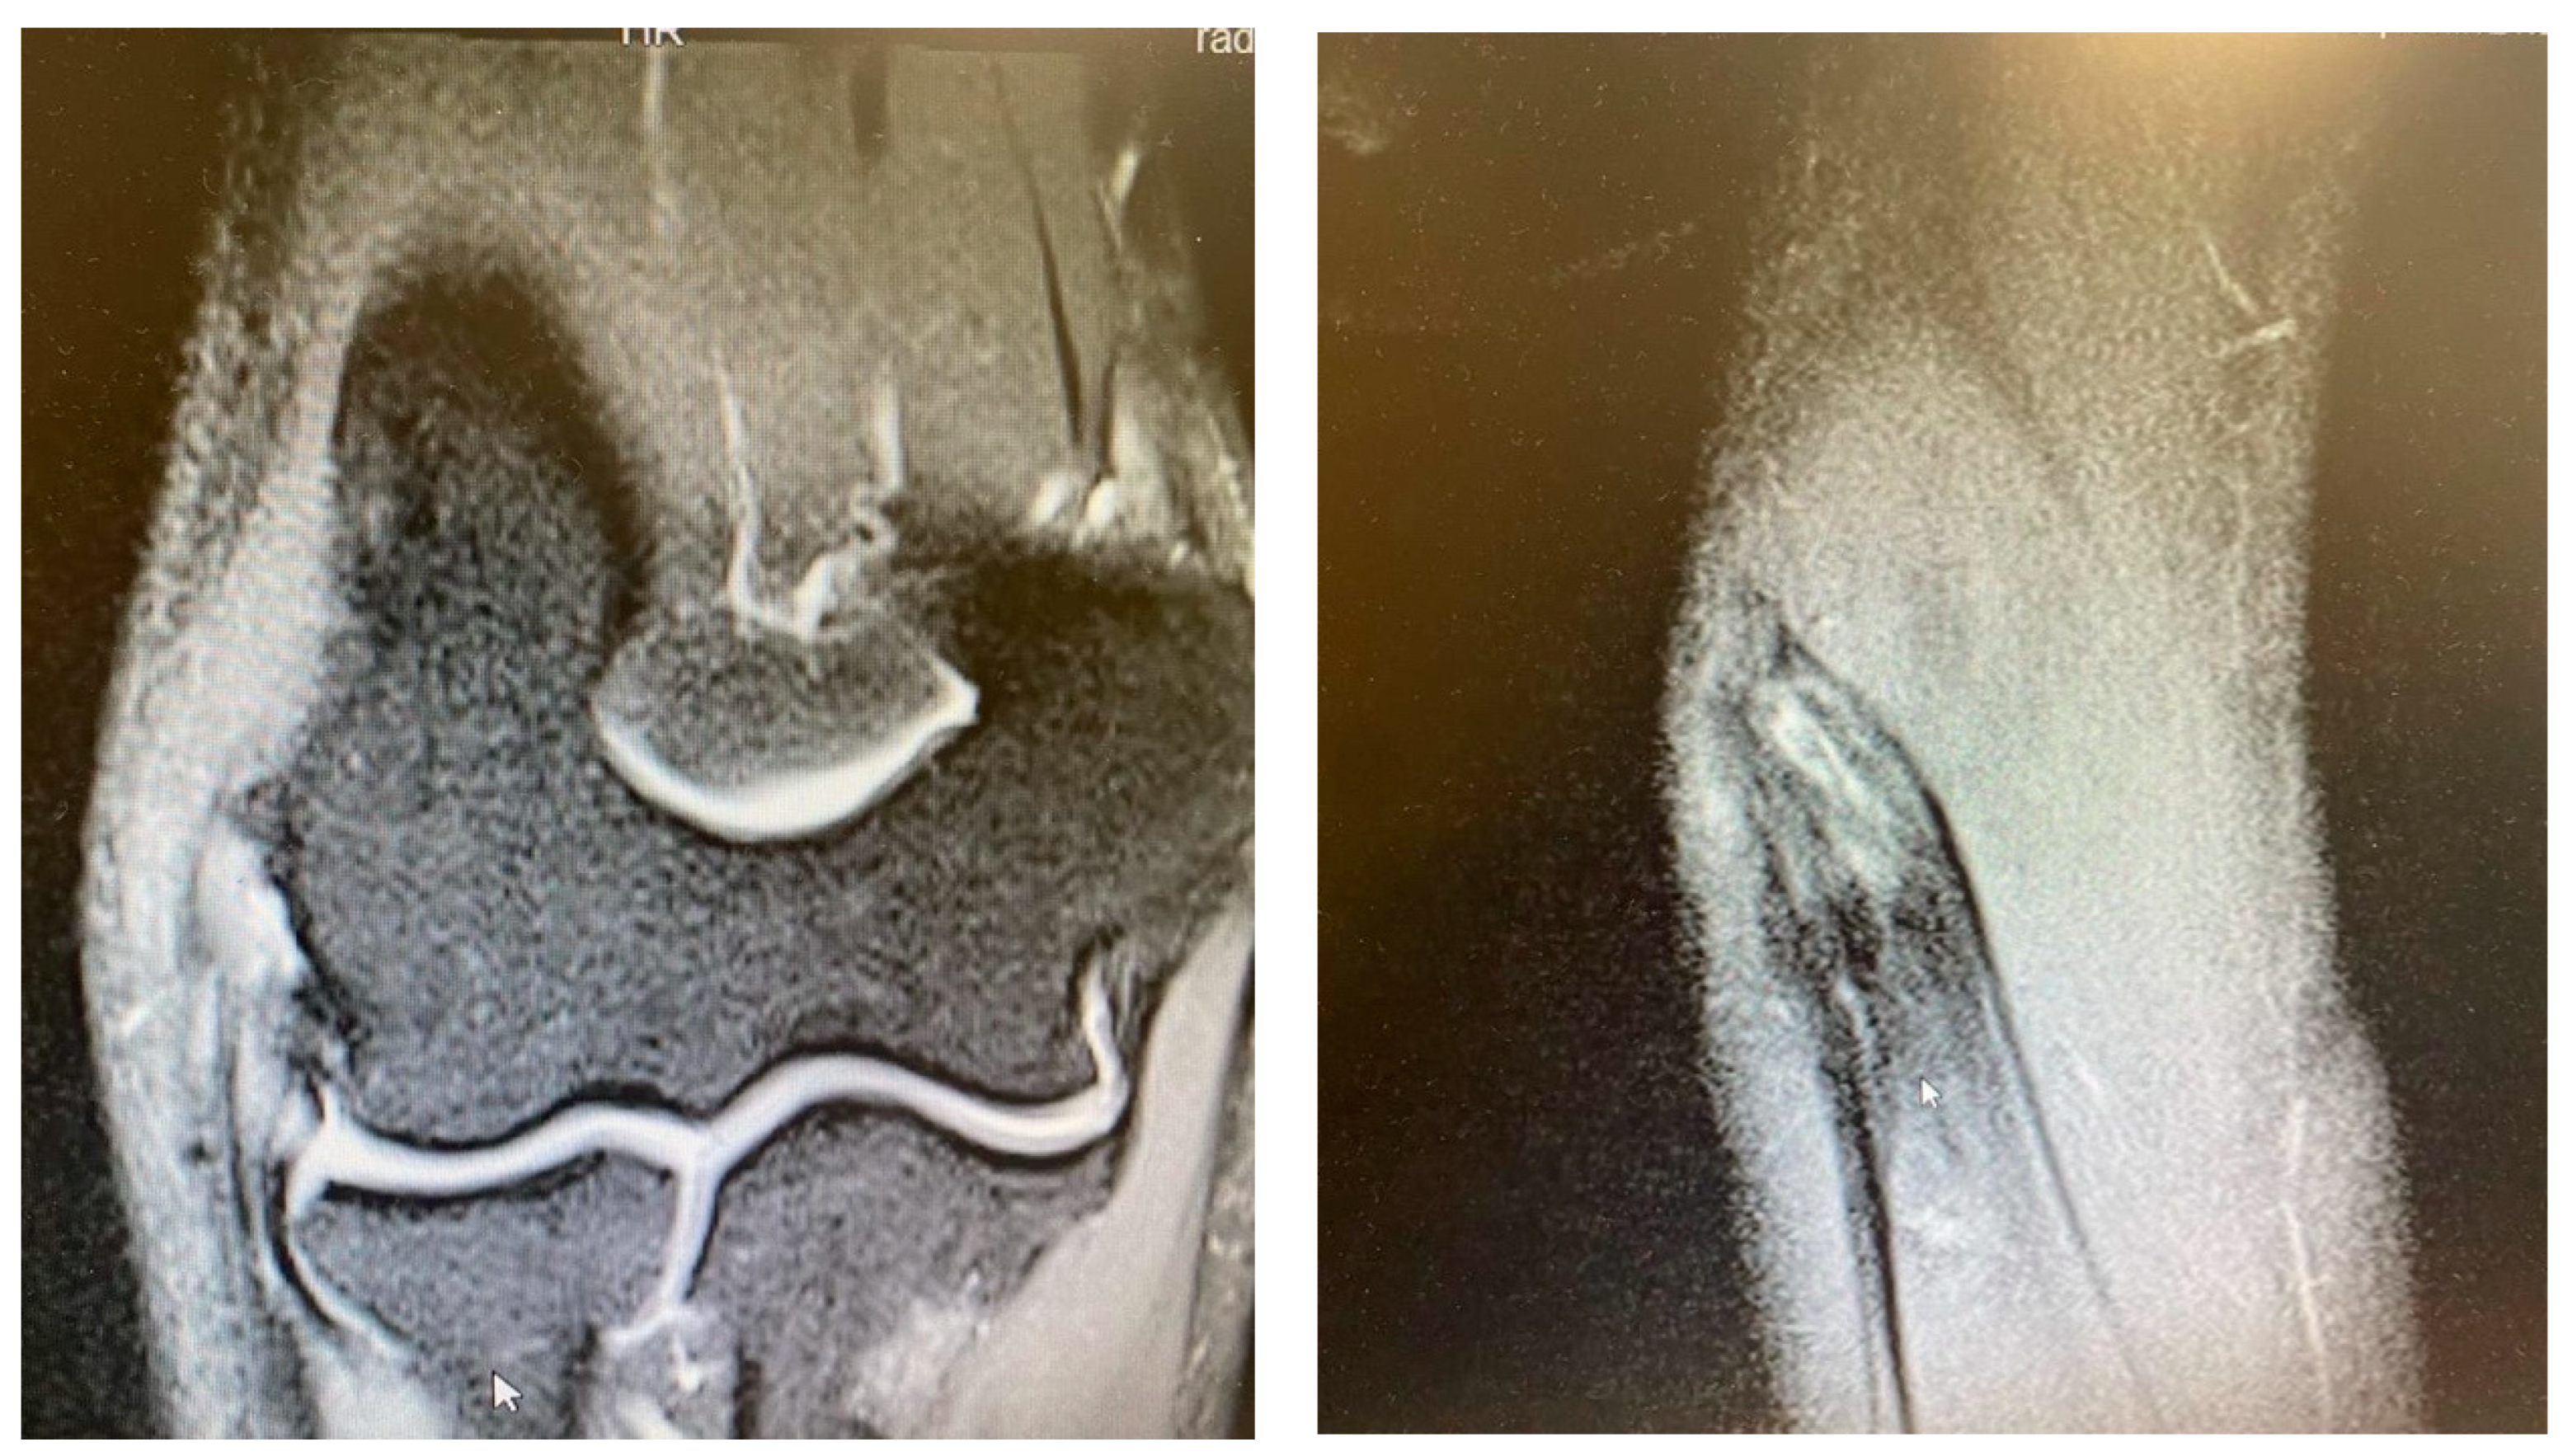

Figure 3.

Extensive partial CEO tear [courtesy of C.K.].

Figure 4.

Complete CEO rupture [courtesy of C.K.].